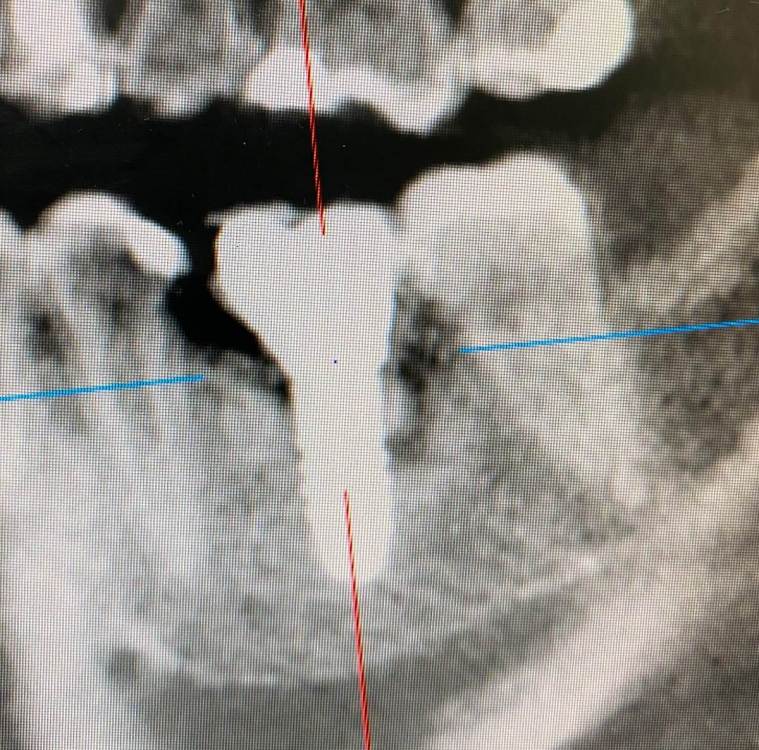

колесников Опубликовано 5 июля, 2022 Поделиться Опубликовано 5 июля, 2022 Здравствуйте коллеги. Год назад попалась публикация где описывался случай как ксеноаугментат секвестрировался спустя 12лет. Мне на днях попался аналогичный случай. Спустя 5 лет(графт bio-oss). Пусковым механизмом, вероятно ,был цемент ,попавший в придесневую шахту после фиксации. Ещё из интересного: интегрированный имплант (mis)удалён ключом на реверс. Вывод: чистый ксено-это не кость. 6 Ссылка на комментарий